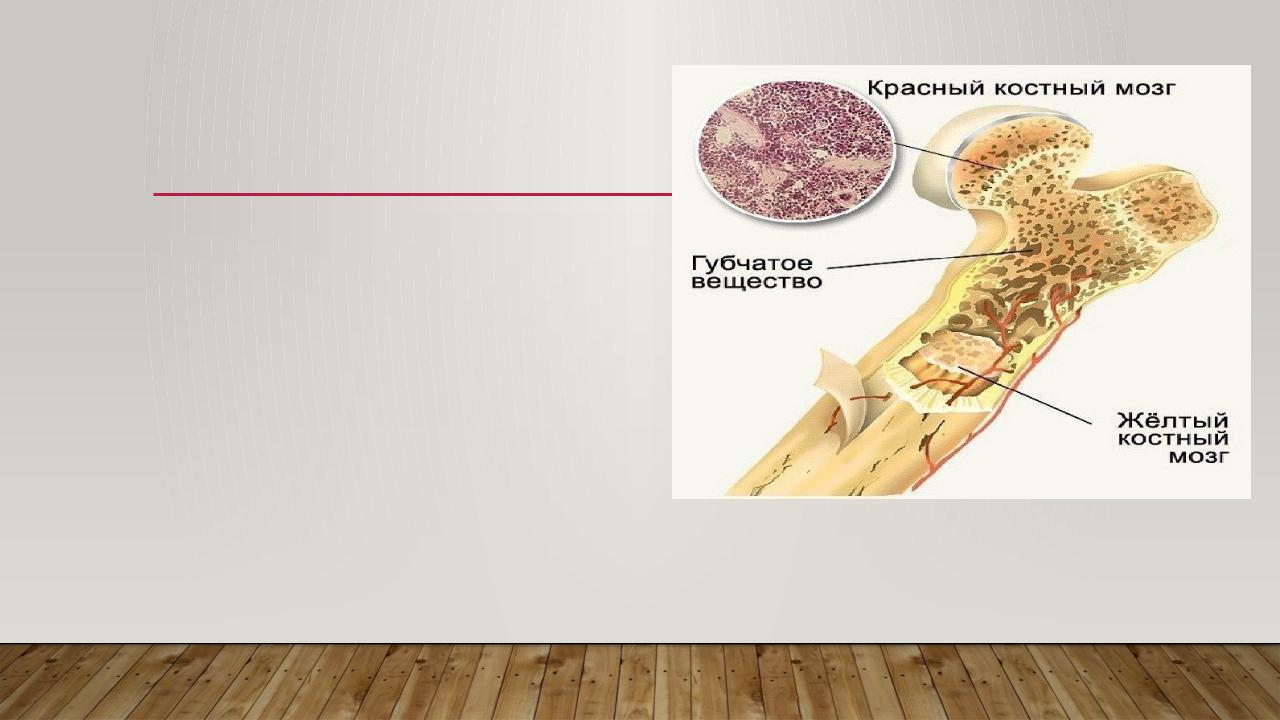

Структура грубоволокнистой костной ткани: наглядные примеры